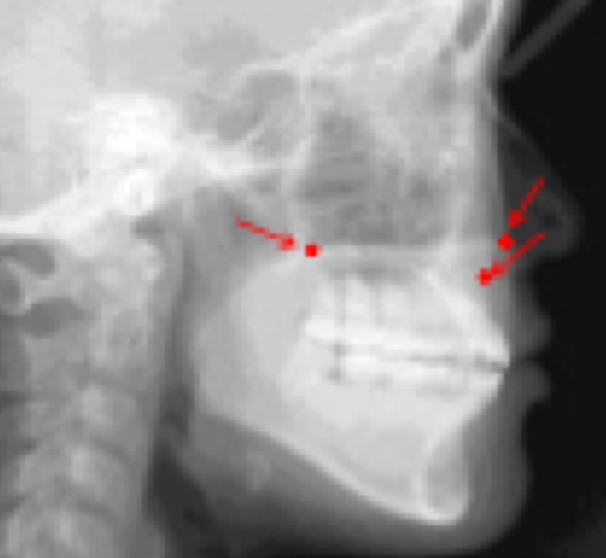

Cranial landmarks (forming cranial base) how can we use it?

Nasion (Na) - anterior point of intersection between nasal and frontal bones

Sella (S) - midpoint of the cavity of sell turcica

–> line between the two forms cranial base

goal - if we assume cranial base is stable, we can see how other structures are positioned relatively

Maxilla Landmarks

ANS - the tip of of anterior nasal spine

PNS - tip of posterior spine of palatine bone at the junction of soft and hard palates

Point A - innermost point of contour of the premaxilla between ANS and incisor tooth